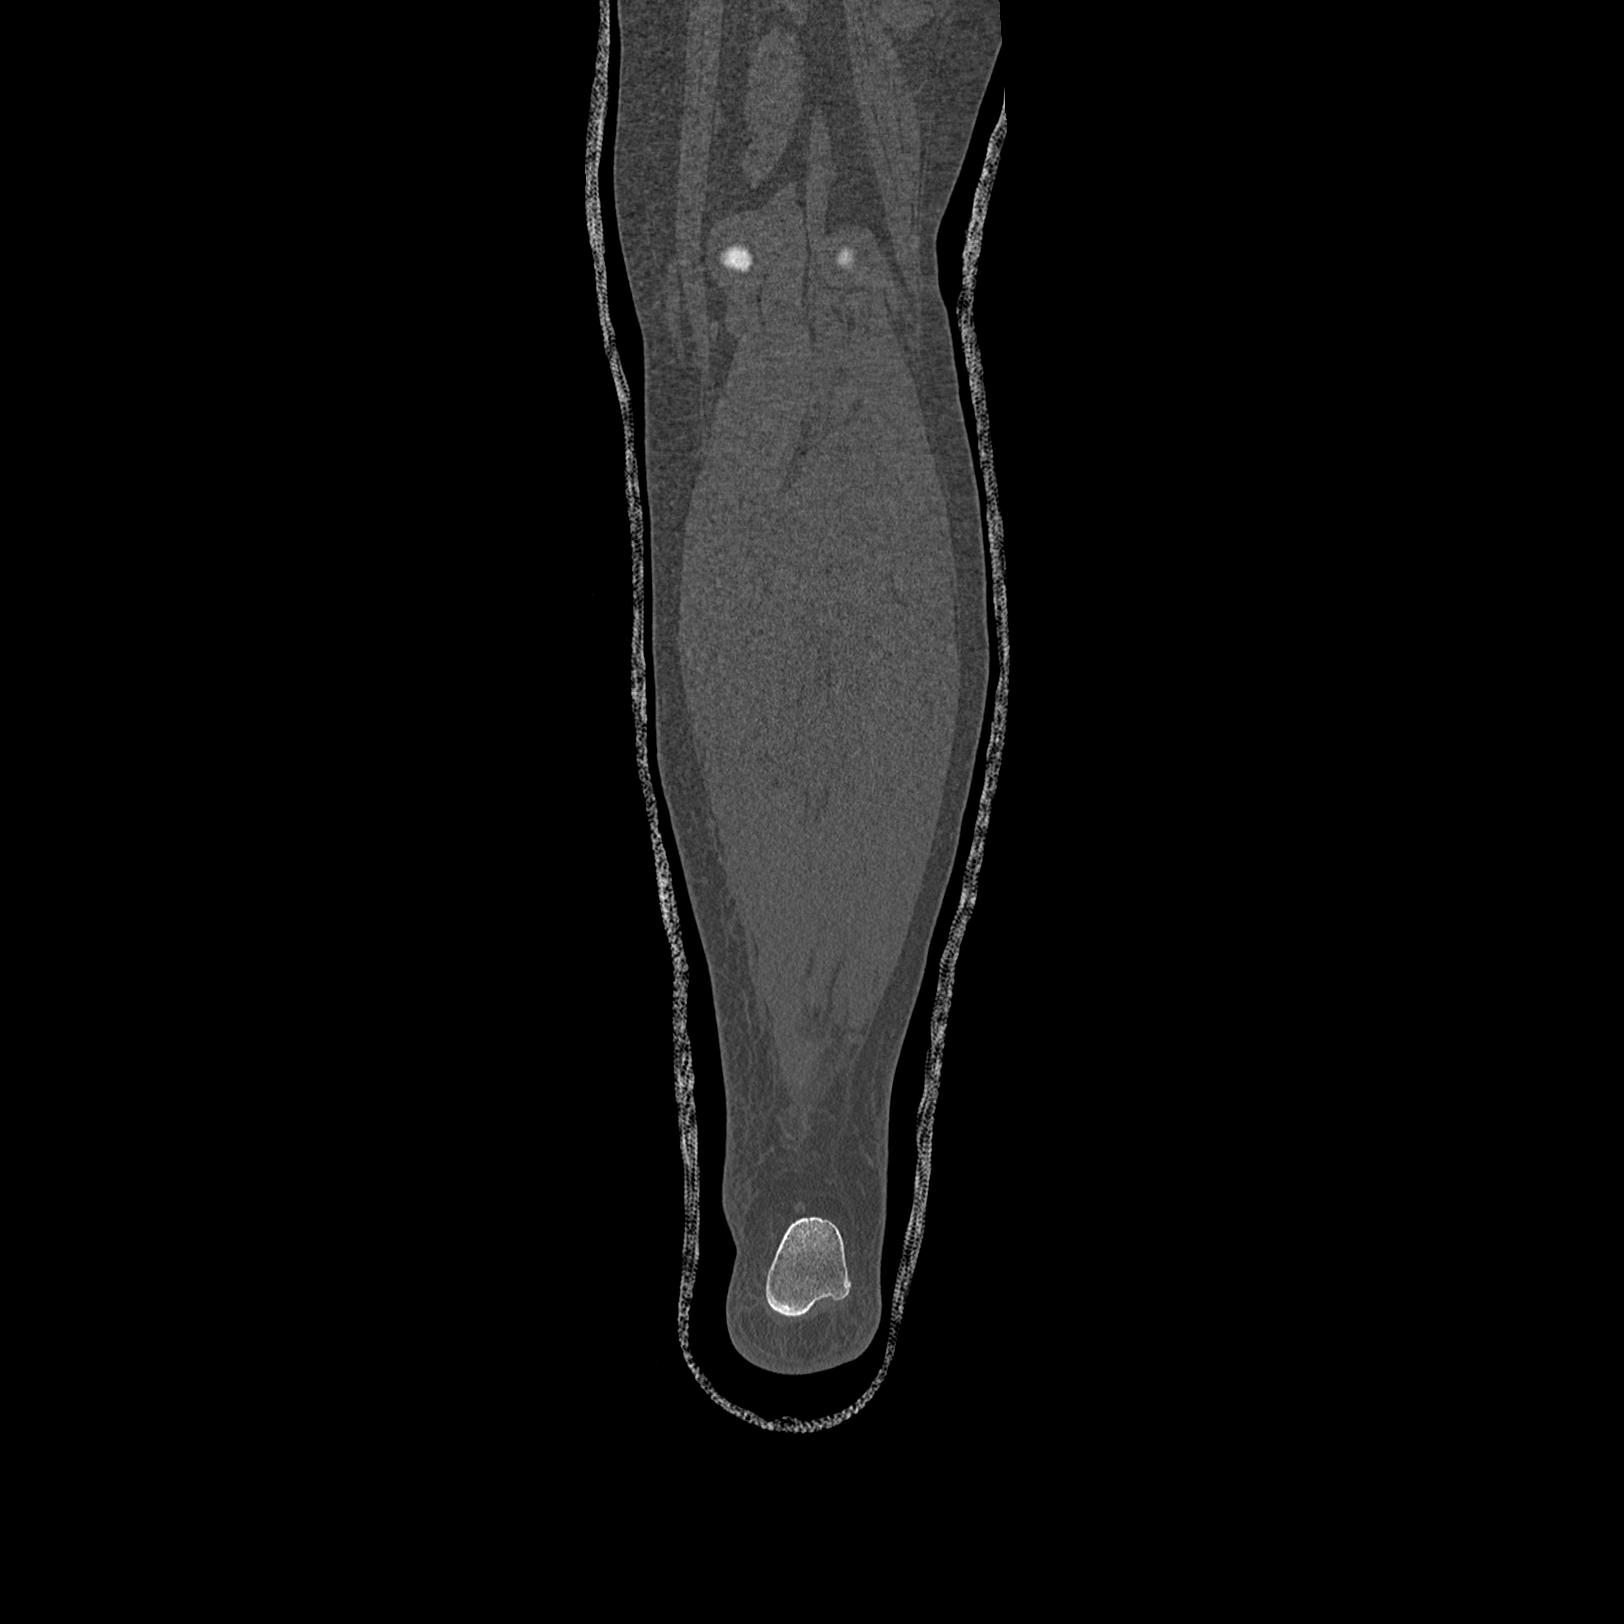

102803 1/12(キウスなし) 1/27 左下腿 4R 30歳女性 左脛骨軸内釘